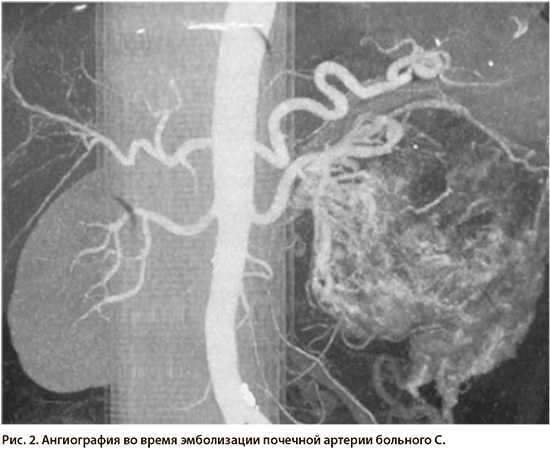

Хирургические процессы при эмболизации гемангиомы на фото